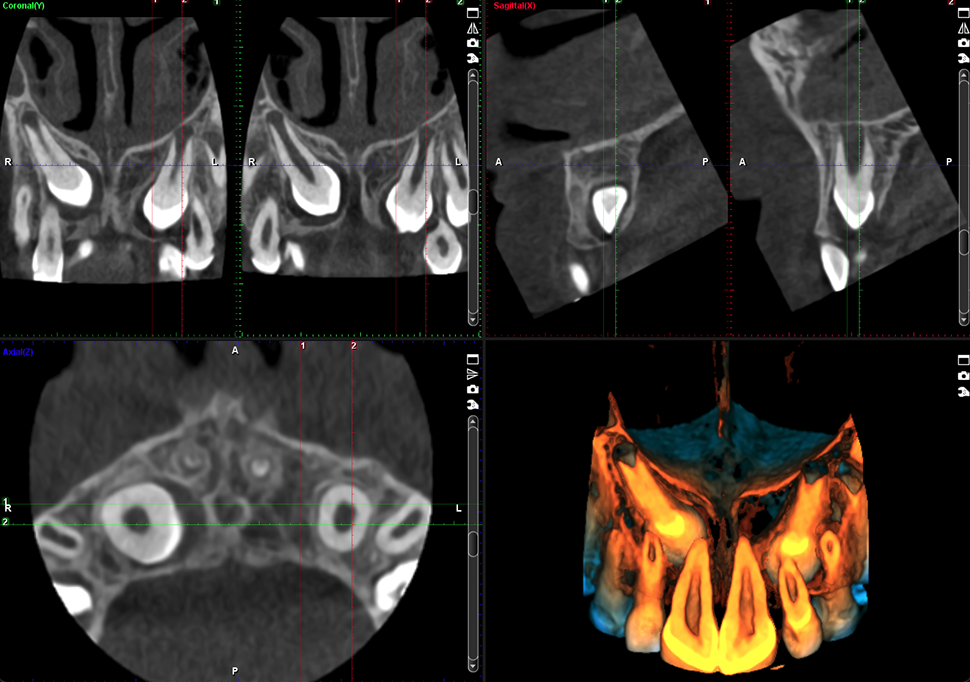

Canino impactado

Volumen 8 x 8